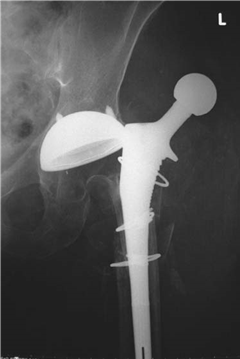

What condition is illustrated here?

Avascular necrosis of the femoral head with segmental collapse.

Can you describe any classifi cation systems for this condition? What stage is shown in the radiographs above?

There are many classifi cation systems described for osteonecrosis of the hip. The Ficat and Arlet (1980) system describes X-ray appearances and is one of the most simple to use:

Stage 1: no bony changes seen on plain X-ray

Stage 2: sclerotic and cystic changes within the femoral head

Stage 3: subchondral collapse and distortion of the femoral head

Stage 4: secondary osteoarthritis with decreased joint space and articular collapse

T he radiographs show Ficat and Arlet stage 4 changes. There is distortion and collapse of the femoral head. The lateral view illustrates the โcrescent signโ associated with subchondral collapse.